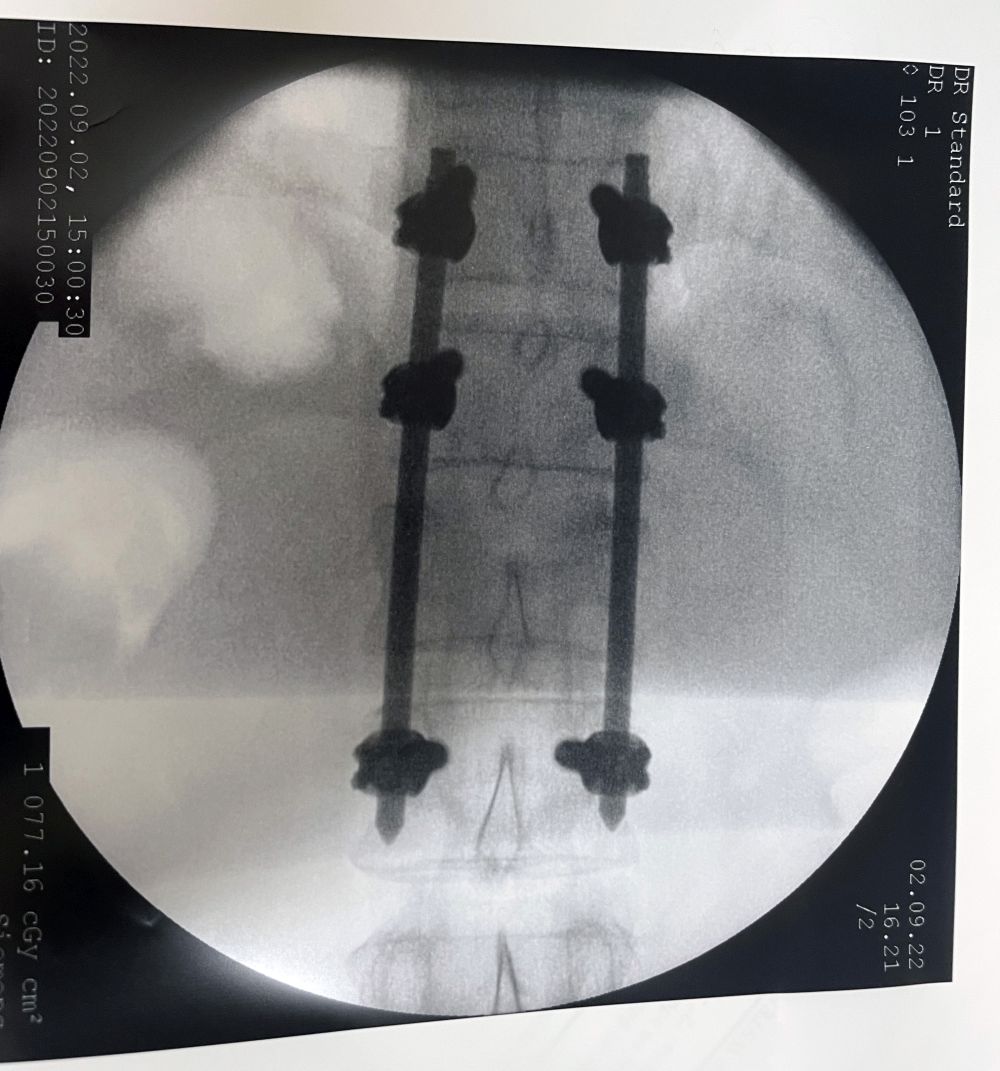

Tylko w ostatnich tygodniach ze złamaniem kręgosłupa zoperowano kilkunastu pacjentów. Operacje były wykonywane nowoczesną, małoinwazyjną metodą przezskórną.

Ta technika pozwala na szybki powrót chorego do sprawności. Już następnego dnia po zabiegu pacjenci stawali na własne nogi, a po kilku dniach samodzielnie opuszczali szpital. Wszystkie operacje odbyły się bez powikłań.